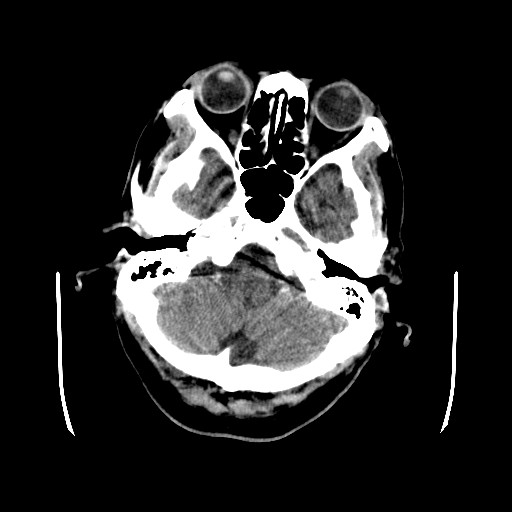

患者,男,70岁,清晨(10小时前)无法自行起床,家人无法唤醒,现昏迷,大小便失禁

左颞枕叶交界区可见类圆形高密度区,边缘可见环形更高密度影,并夹杂有点状钙化影,占位效应明显,未见明显水肿影,考虑脑膜瘤出血

左颞枕叶交界区可见类圆形高密度区,边缘可见环形更高密度影,侧脑室后角明显受压而周围未见明显水肿.考虑脑膜瘤伴出血可能性大不排外血管畸形.建议mr进一步检查.

左侧颞枕叶交界区见类圆型等高密度混杂影,边缘可见高密度影环绕,同侧侧脑室后脚受压变形,周边围见明显水肿影. 结论:脑膜瘤首先考虑.

左颞枕叶交界区的类圆形高密度区首先考虑脑膜瘤卒中,病人左侧小脑半球的还有多个囊性低密度,要考虑同时伴有梗塞的可能。